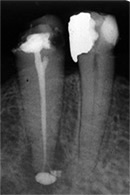

Dieser Zahn wurde schon geraume Zeit zuvor von einer Kollegin im Notdienst eröffnet und anschlies­send mit einer aufwendigen Amal­gamrestauration ästhetisch an­sprechend wieder verschlossen. (Bild 1) Uns blieb noch WK/WF, was bei massiver Überstopfung der hin­teren Wurzel auch gelang (Bild 2).

"Überstopfen ist immer noch besser als Unterstopfen" laut Koçkapan. OK, hier wurde des Guten aber ganz eindeutig zuviel getan.

Also direkt neben dem Zahn das Zahnfleisch ein wenig angehoben und zur Seite gedrängt und dann mit einem scharfen Löffel den Überschuss vollständig entfernt.

Schon 8 Monate später ist eine deutliche Verbesserung der Gesamt­situation unverkennbar (Bild 3). Verlorengegangene Knochensubstanz wurde in Teilen schon wieder aufge­baut, doch ist noch gar nichts entschieden. Schaun mer also ma'.